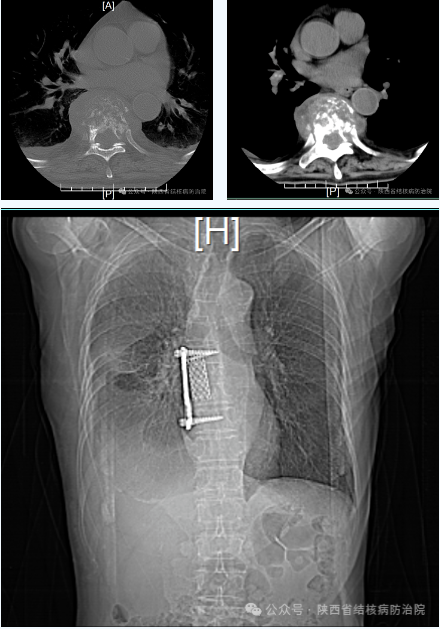

经过抗结核治疗3周、治疗基础疾病、改善身体状况后,我们建议患者行手术治疗,家属及患者非常配合。考虑到患者高龄,基础疾病多,椎体破坏较重,我们制定了详尽的手术计划,尽可能保证患者围手术期的安全。我们选择“开胸”入路行前路手术清除病灶、解除椎管压迫,椎间植骨、钢板螺钉内固定术,手术时间短,损伤小,出血量少,手术视野大,术后恢复快。术后,辛大爷的胸背部疼痛消失了,排尿恢复了,下肢活动自如了。术后三周,辛大爷开始下床活动了,“陕西省结核病防治院结核外科救了我老头子的命啊!”辛大爷激动地说。